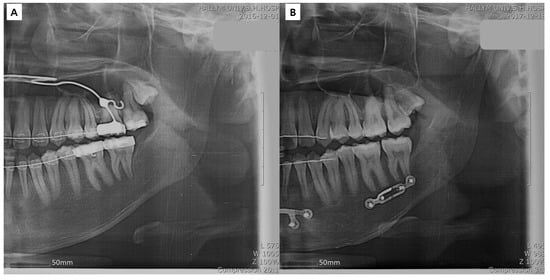

2.2. Virtual Surgery (VS), Designing and Creating Patient-Specific Materials, and Actual Surgery

2.2.2. Surgery